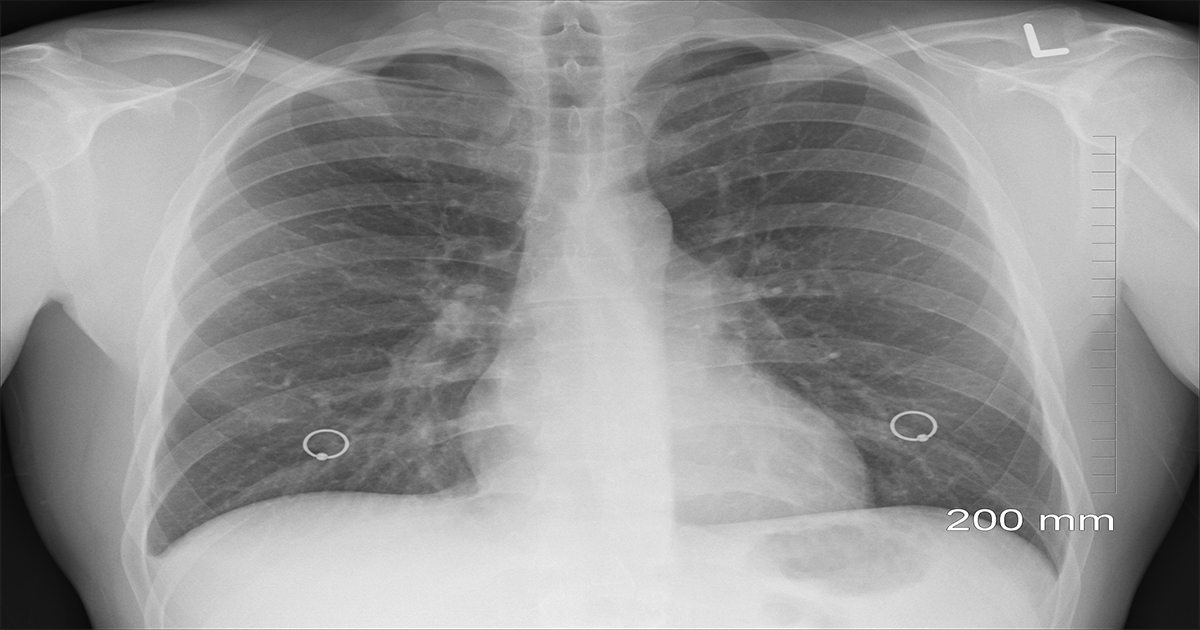

Asbestos is a naturally occurring mineral that was widely used in construction, manufacturing, and other industries for its heat-resistant and durable properties. Unfortunately, exposure to asbestos fibers can lead to serious health conditions, most notably mesothelioma, a rare and aggressive form of cancer that affects the lining of the lungs, abdomen, or heart.

• Lung cancer

• Asbestosis

• Pleural disease (lung lining damage)